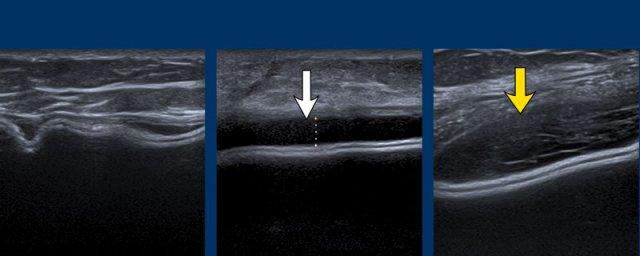

Dấu hiệu Oreo ngược

Vỏ bọc của túi độn có thể được nhìn thấy như một chiếc bánh Oreo lật ngược. Đường trắng đầu tiên là mặt tiếp xúc bên ngoài của vỏ bọc và đường trắng thứ hai là mặt tiếp xúc bên trong giữa vỏ bọc và gel Silicone (mũi tên vàng).

Giữa lớp ngoài của vỏ bọc và bao xơ xung quanh tồn tại một khoang ảo có thể được lấp đầy và giãn rộng.

Bao xơ được nhìn thấy tách biệt khỏi vỏ bọc như một đường trắng riêng biệt nằm phía trước vỏ bọc (mũi tên trắng).

Vỏ bọc và bao xơ cùng nhau được gọi là phức hợp vỏ bọc-bao xơ.

Dấu hiệu bậc thang (Step off sign)

Dấu hiệu bậc thang là một xảo ảnh gây ra bởi tốc độ truyền âm thấp hơn của sóng siêu âm qua Silicone (970 m/giây trong gel Silicone so với 1540 m/giây qua nước).

Hệ quả là thành ngực có vẻ sâu hơn ở vị trí tương ứng với túi độn.

Xảo ảnh này không xuất hiện trong các túi độn chứa nước muối sinh lý.